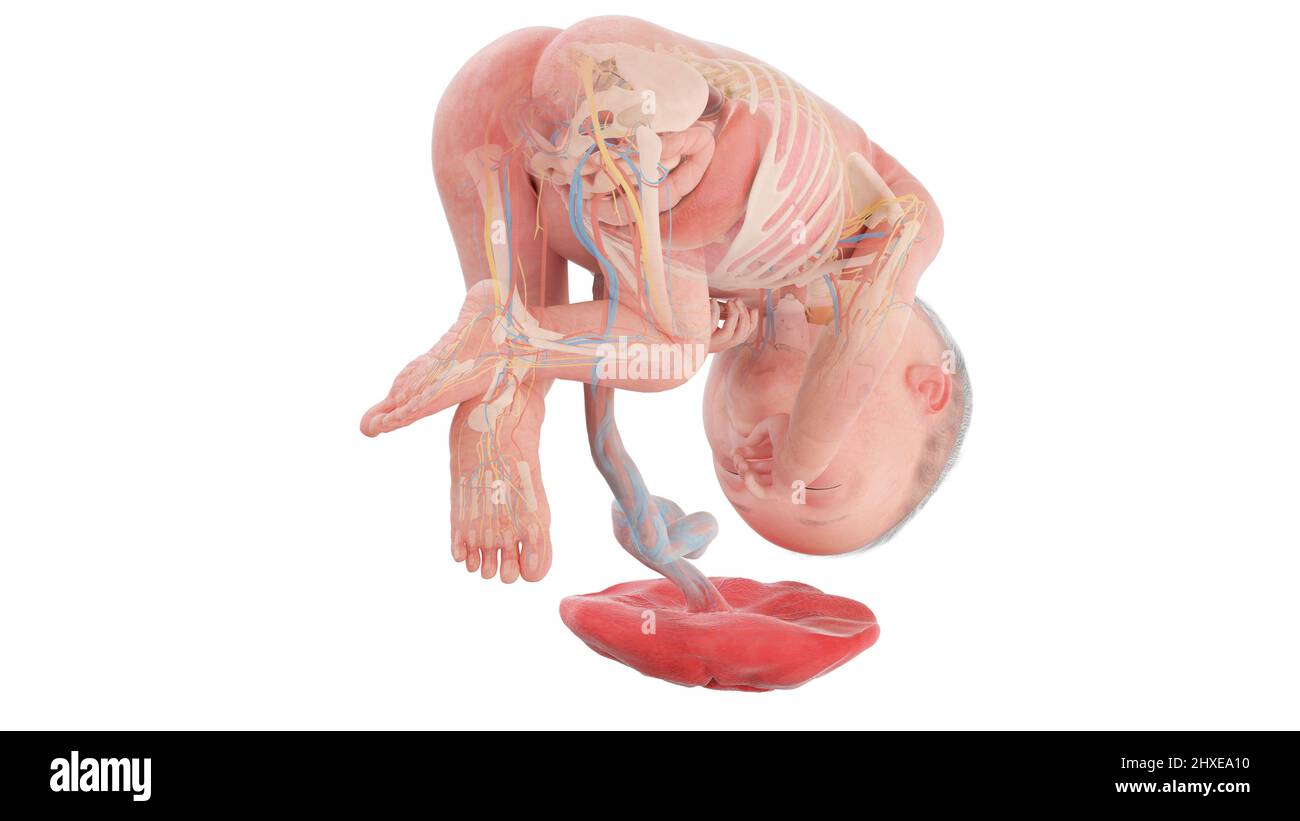

Anatomia del feto umano alla settimana 27, illustrazione Foto Stockhttps://www.alamy.it/image-license-details/?v=1https://www.alamy.it/anatomia-del-feto-umano-alla-settimana-27-illustrazione-image463765820.html

Anatomia del feto umano alla settimana 27, illustrazione Foto Stockhttps://www.alamy.it/image-license-details/?v=1https://www.alamy.it/anatomia-del-feto-umano-alla-settimana-27-illustrazione-image463765820.htmlRF2HXEA10–Anatomia del feto umano alla settimana 27, illustrazione

Anatomia del feto umano alla settimana 27, illustrazione Foto Stockhttps://www.alamy.it/image-license-details/?v=1https://www.alamy.it/anatomia-del-feto-umano-alla-settimana-27-illustrazione-image463765855.html

Anatomia del feto umano alla settimana 27, illustrazione Foto Stockhttps://www.alamy.it/image-license-details/?v=1https://www.alamy.it/anatomia-del-feto-umano-alla-settimana-27-illustrazione-image463765855.htmlRF2HXEA27–Anatomia del feto umano alla settimana 27, illustrazione